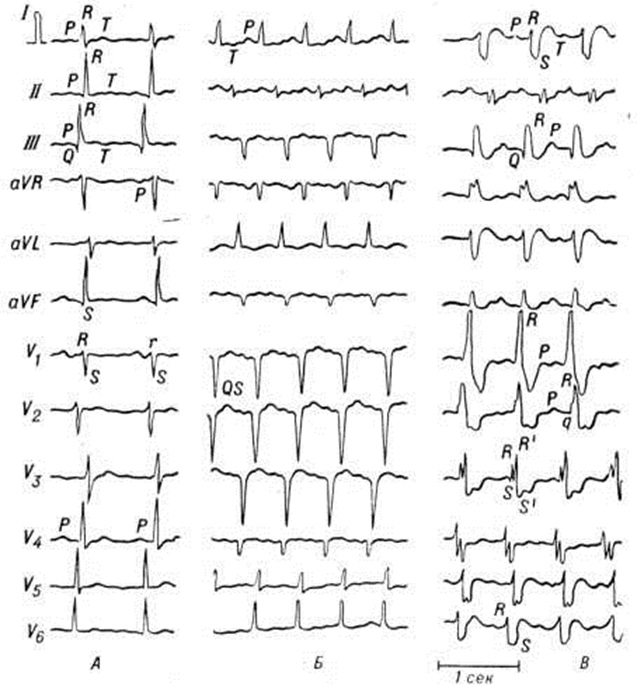

Альтерация клеток специфической проводящей ткани миокарда и сопутствующие воспалению электролитные сдвиги являются причиной часто наблюдающихся при Миокардит разнообразных нарушений ритма сердца и проводимости. Неглубокие дистрофические изменения ведут к развитию блокад на разных уровнях проводящей системы с односторонним проведением возбуждения, то есть создают предпосылки для повторного входа возбуждения и развития мерцательной аритмии (смотри полный свод знаний). Более выраженные изменения являются причиной нарушений проводимости, проявляющихся атриовентрикулярной блокадой и блокадой отдельных пучков внутрижелудочковой проводящей системы (смотри полный свод знаний Блокада сердца).

Гистологический картина Миокардит отражает особенности его природы и стадию процесса. Систематизация по преобладающим гистологический проявлениям позволяет выделить 5 вариантов Миокардит: паренхиматозный, дистрофический, обозначавшийся как аллергическая дистрофия миокарда; воспалительно-инфильтративный; некротический, или деструктивный; гигантоклеточный; смешанный (цветной рисунок 4, 5, 6). В особую разновидность выделена так называемый васкулярная форма Миокардит, клинически проявляющаяся симптомами коронарной недостаточности, а морфологически — преобладанием картины васкулита (смотри полный свод знаний). С учётом относительной специфичности некоторых гисто л. изменений Миокардит подразделяют на 3 основные формы: неспецифический, гранулематозный (специфический) и гигантоклеточный Миокардит